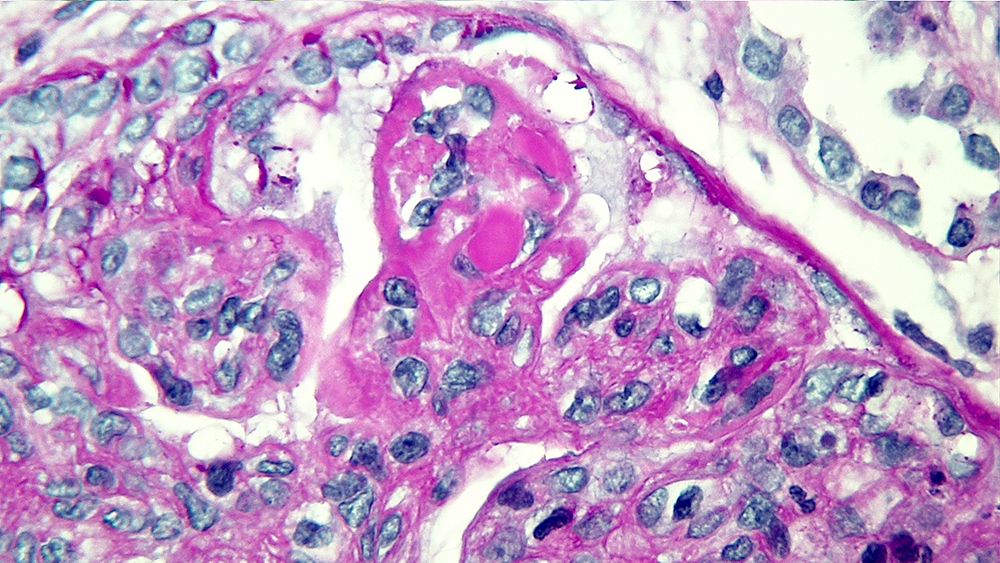

Microscopic (histologic) images

Contributed by Alexei Mikhailov, M.D., Ph.D.

- LN class V: thickening of the glomerular capillary walls, microspikes and domes may be associated with any mesangial alterations

- PAS special stain is the most useful staining method in every LN class to evaluate mesangial and endocapillary changes

- PAMS (Jones Silver) special stain is most useful in LN class V and emphasizes capillary wall thickening and neomembrane formation (microspikes and domes)

- Class V, membranous LN: global or segmental subepithelial immune deposits at any stage () by light microscopy or immunofluorescence / electron microscopy, with or without mesangial alterations